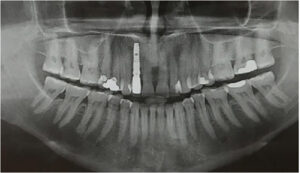

Після того, як виключені всі протипоказання, проводяться стандартні для всіх хірургічних втручань лабораторні дослідження – загальноклінічний і біохімічний аналіз крові, визначаються показники згортання крові, а також аналізи на ВІЛ-інфекцію, гепатит В і С, сифіліс. З інструментальних методів дослідження використовується рентгенографія (ортопантомограмма – панорамний знімок зубів), при необхідності – КТ або МРТ верхньої і нижньої щелепи.

Таким чином, на цьому терміні доречно проведення рентгенологічного обстеження з метою визначення обсягу сформованих тканин, їх рентгенологічної контрастності і щільності, тобто ступенем мінералізації і придатності до установки імплантатів.

Комп’ютерна томографія зубів – досконалий метод дослідження, який дозволяє лікарю визначати параметри будови зубощелепної системи, що дає більше інформації про аномальні патології. Це відносно нова методика діагностики в галузі стоматології. Але незважаючи на це, за короткий проміжок часу вона стала широко прийнятною.

Комп’ютерна томографія дозволяє отримувати тривимірні знімки щелепи і зубів. Завдяки цьому можна з великою ймовірність визначити точну проблему і призначити ефективне лікування. КТ дає можливість зрозуміти, що відбувається всередині зубів. Томографія стала невід’ємною частиною лікування серйозних травм щелепи, коли, в прямому сенсі її необхідно зібрати по частинах. Метод знайшов своє місце в усіх галузях стоматології.

Основними показаннями до даної діагностики є протезування і лікування деяких хвороб. Вона може бути застосована для імплантології, ендодонтії, пародонтології, ортодонтії та гнатології.

- У імплантології КТ необхідно зробити виміри щелепи, для установки імпланта.